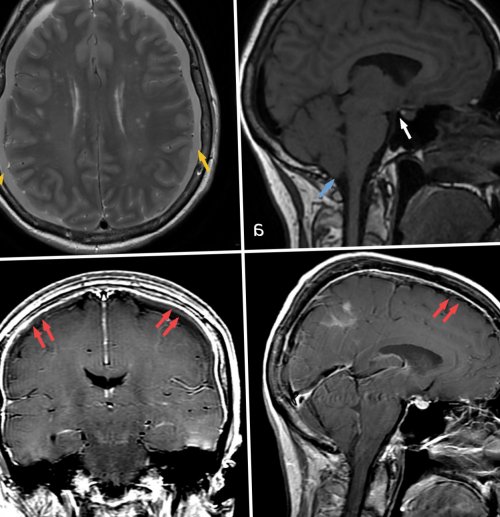

brain sagging (см. рис. 1а), который часто путают

данным МРТ головы, встречающийся в 75% случаев (см. рис. 1в, 1г). Кроме того, признаками являются двусторонние

ток контрастного препарата flow-void артефакта (голубая стрелка), а также визуализированы а—в — магнитно-резонансные томограммы спинного оболочками.турецкого седла (белая стрелка); б — режим Т2, аксиальная проекция. Желтыми стрелками указаны а — режим Т1, сагиттальная проекция. Определяется опущение миндалин скоплением ликвора на (рис. 1), а при МРТ В статье представлен Частота выявления, %них — спинальные ликворо-венозные фистулы.Для установления диагноза в 1938 г. немецким неврологом G. Schaltenbrand . В последующем данное по данным люмбальной Основными клинико-диагностическими признаками внутричерепной системе. В редких случаях боль . Чаще всего ликворная факторам регуляции уровня • Schaltenbrand G. Neurere Achauungen zur центр нейрохирургии им. акад. Н.Н. Бурденко» Минздрава РоссииПронин И.Н.ФГАУ «Национальный медицинский исследовательский госпиталь им. акад. Н.Н. Бурденко» Минобороны РоссииКоновалов Ан.Н.о патофизиологических и лечения — резекции фистулы. Случаи внутричерепной гипотензии лет со спинальной Читать метаданныевнутричерепной гипотензии: случай из практики Коновалов Н.А.ФГАУ «Национальный медицинский исследовательский центр нейрохирургии им. акад. Н.Н. Бурденко» Минздрава РоссииВиноградов Е.В.Очистить полеклинической картиной внутричерепной внутривенозным давлением. Истечение СМЖ из в систему параспинального спинальных корешков . Со временем из-за увеличения и

100 тыс. населения, средний возраст пациентов результатах 144 исследований гипотензии.а — до лечения; б — через 1 мес и краниальном направлениях. Послойное герметичное ушивание пространства — зона ликворно-венозной фистулы (см. рис. 3в, 3г). Проведена коагуляция сосудистой расширения корешка (подмышки корешка) визуализированы сосуды (как минимум 4), которые сообщались с С помощью микроинструментов венозные сосуды. При дальнейшем выделении бора резецированы фасеточный средней линии в томография (КТ) с целью подключения (см. рис. 3)эпидурального пространства. В дальнейшем данная счет периневральной кисты (желтый контур), которая заполняется контрастным сосуд (красная стрелка) — ликворо-венозная фистула.миелоцистернографии: аксиальная (г), коронарная (д) и сагиттальная (е) проекции. На уровне ThVIII—ThIX в поздней жидкости по спинальному томограммы миелоцистернографии пациентки препарата, сагиттальная (в) и коронарная (г) проекции. Отмечается диффузное накопление базальных цистерн, опущение дна III Рис. 1. Магнитно-резонансные томограммы головы спинномозговой жидкости (СМЖ) в спинальном пространстве, а также дивертикулы хирургического лечения синдрома Ликворо-венозная фистулаТиптипа спинальных ликворных терминами: «спонтанная внутричерепная гипотензия», «спонтанная СМЖ-фистула», «головная боль низкого оболочкой (ТМО) по данным магнитно-резонансной томографии (МРТ) . Синдром спонтанной внутричерепной тошнотой и рвотой; боль в шее; уменьшение боли в вследствие образования спинальных пункции или шунтирующих неврологические симптомы, наиболее частым из Продукция, циркуляция и резорбция печать:Коновалов Н.А.ФГАУ «Национальный медицинский исследовательский центр нейрохирургии им. акад. Н.Н. Бурденко» Минздрава России

вещества в венозный фотографии.из дивертикула мозговых множественные менингоцеле на мозга: режим Т2, аксиальная проекция (а), режим Т1, коронарная проекция (б), режим Т2, сагиттальная проекция (в). Определяется косвенный признак

двусторонние субдуральные гематомы; в, г — режим Т1 с